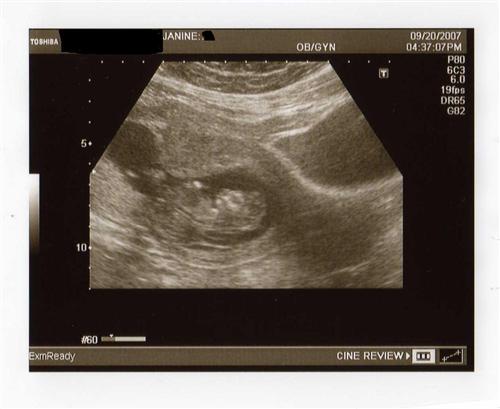

Does anyone know what the other black circle to the right is? We didn't think to ask. If it was another baby, it would be full, so I don't think it is that.

Could it be a fluid sac, thats what mine was.

I agree. I had a small black sac and I was told mine was also a fluid sac and was completely normal. I'm almost positive it's not another baby. My 12 week sonograms clearly depict two whole little people!